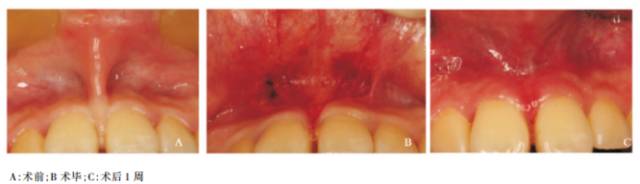

舌系带矫正术,使用激光手术出血少,术后无瘢痕,不需要缝合和拆线。使用激光口腔前庭修整术不需要传统的打包,缩短手术步骤。